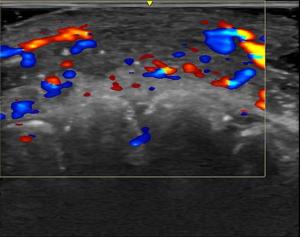

Ultrasound Renal Denervation System for Hypertension Garners CMS National Coverage Determination